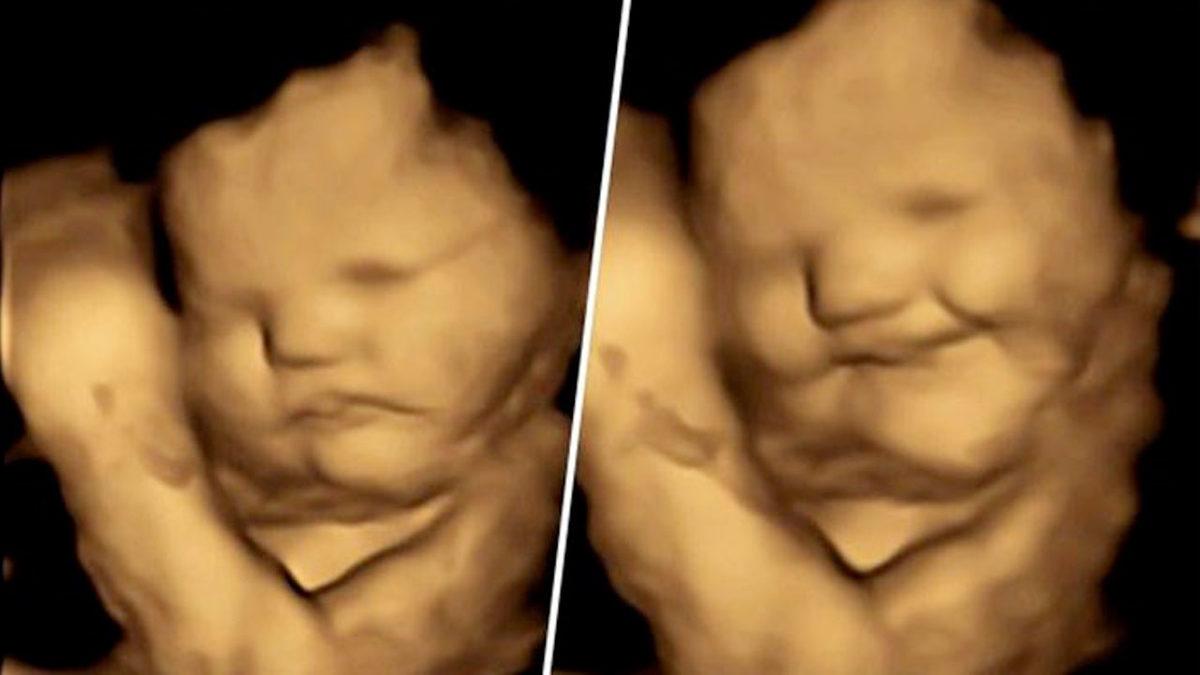

Bebekler lahana tadı aldıklarında somurtuyor, havuç tadı aldıklarında gülüyordu:

- Bebeklerin anne karnında 4 boyutlu çekilen ultrason görüntüsü.

Bilim insanları, çalışma kapsamında 70 anneyi iki gruba ayırdı ve bu gruplara kapsül halinde havuç veya karalahana yedirdi. 30 anne ise herhangi bir özel gıda tüketmeksizin kontrol grubu olarak ele alındı. Annelerin karnında bulunan bebeklerin, anne havuç sindirdiğinde daha ‘neşeli’ bir yüz ifadesi yaptığı görülürken, karalahana sindirildiğindeyse bebeklerde daha ağlamaklı yüz ifadesi görüldü.